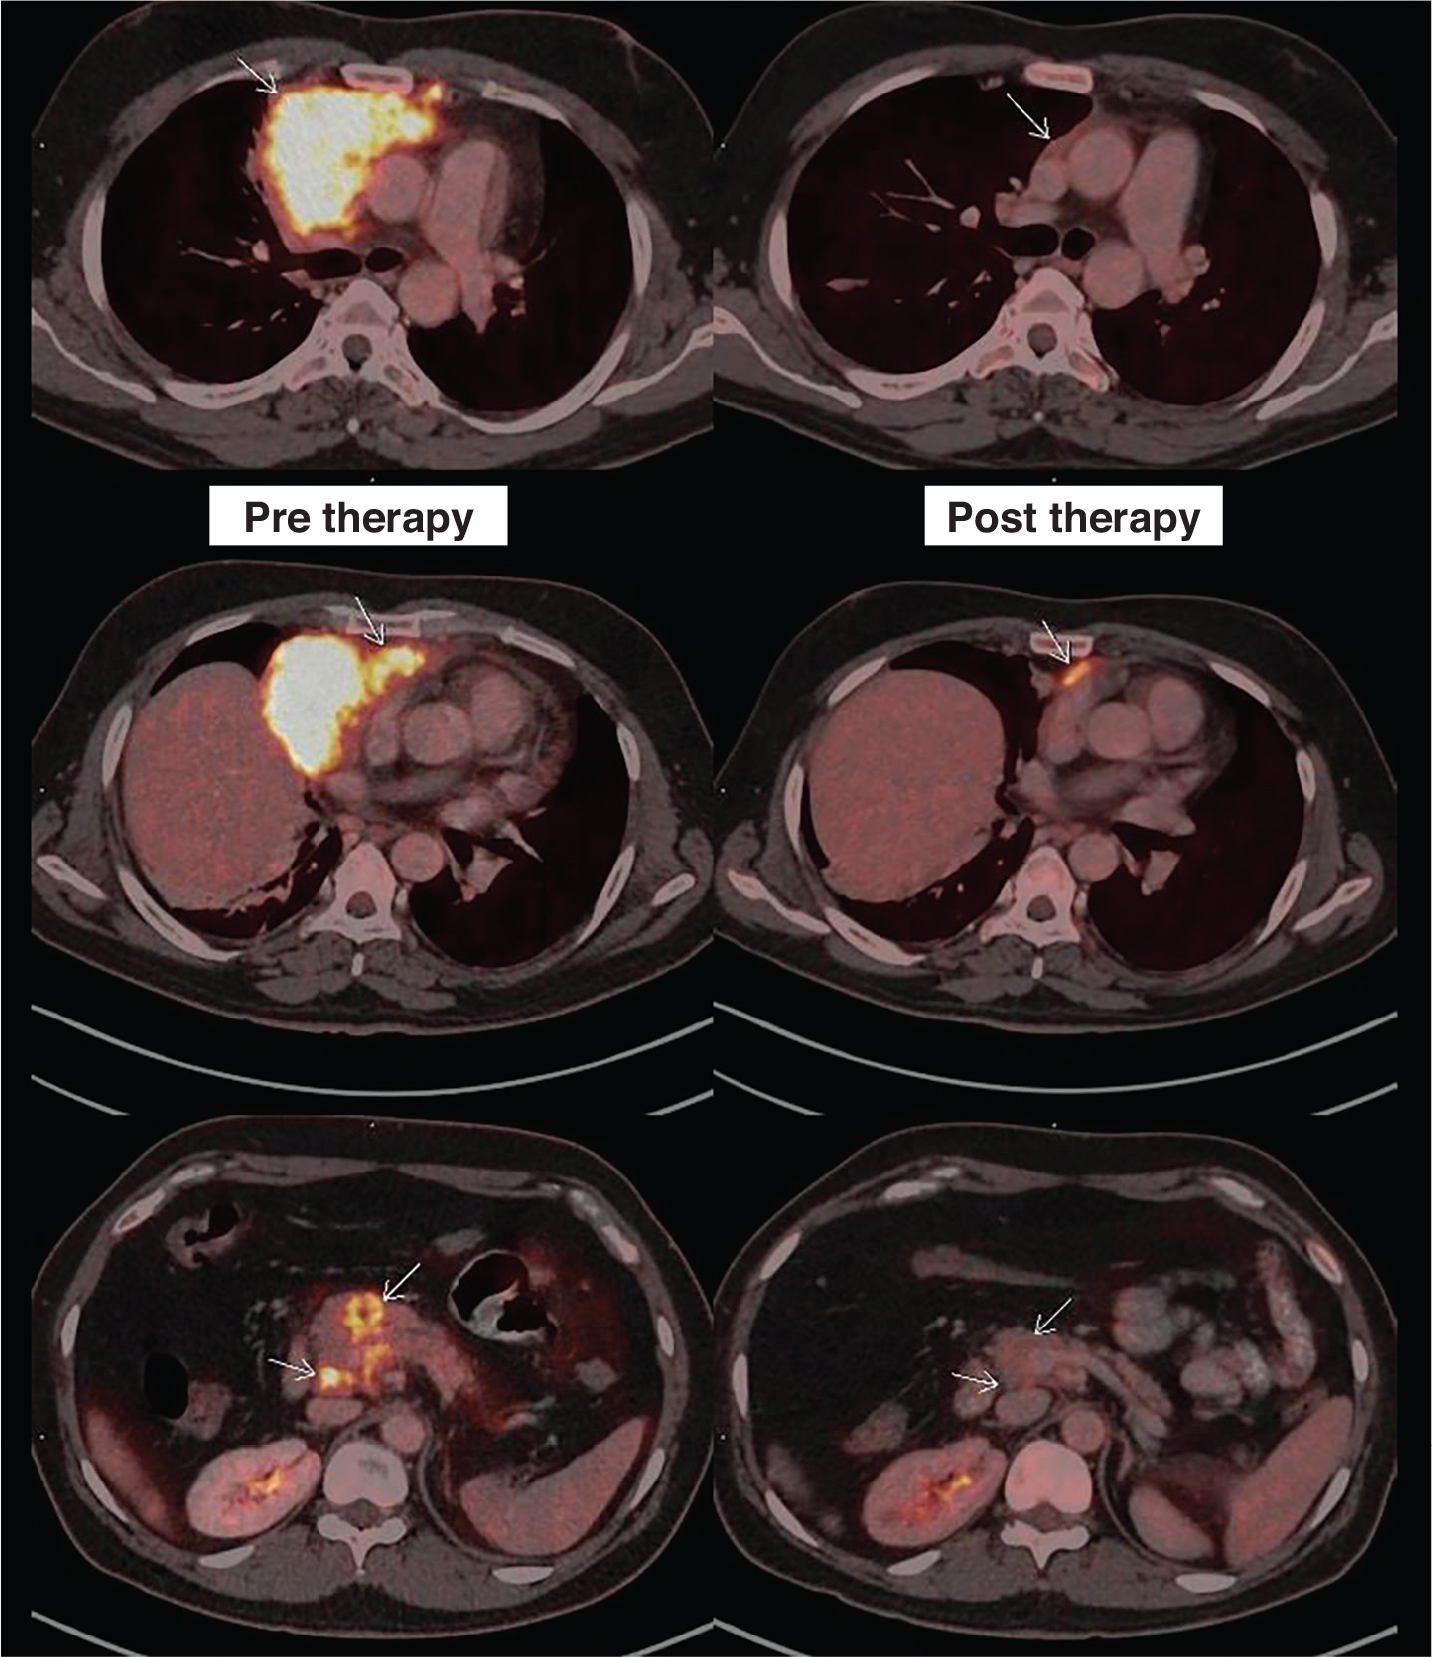

Fig 5

Figure 5. Staging and interim response assessment 18F-FDG PET/CT scans. 18F-FDG PET/CT images include fused axial PET/CT of the patient taken during staging on the left column and interim response assessment after 3 cycles of chemotherapy on the right column (comparative lesions marked with small white arrows). First row showing complete resolution of the bulky component of the disease. Second row showing persistent minimal metabolically active residual disease (Deauville’s score 4) abutting the pericardium and third row showing complete resolution of the pancreatic lesion and adjoining peripancreatic lymph node.